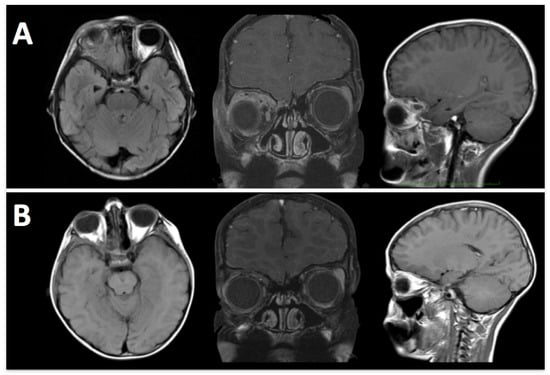

By removing the orbital roof and lateral wall, the E-SRA technique allows for transcranial access to extraconal lesions, including those with an ethmoidal extension. This expanded access enables surgeons to reach tumors in challenging locations (Figure 2).

Figure 2. A 6-year-old boy was treated with orbital Ewing’s sarcoma suspicion. (A) Pre-operative MRI shows an extraconal lesion extended medially until ethmoidal cells. (B) Post-operative MRI confirms the removal of tumoral tissue.